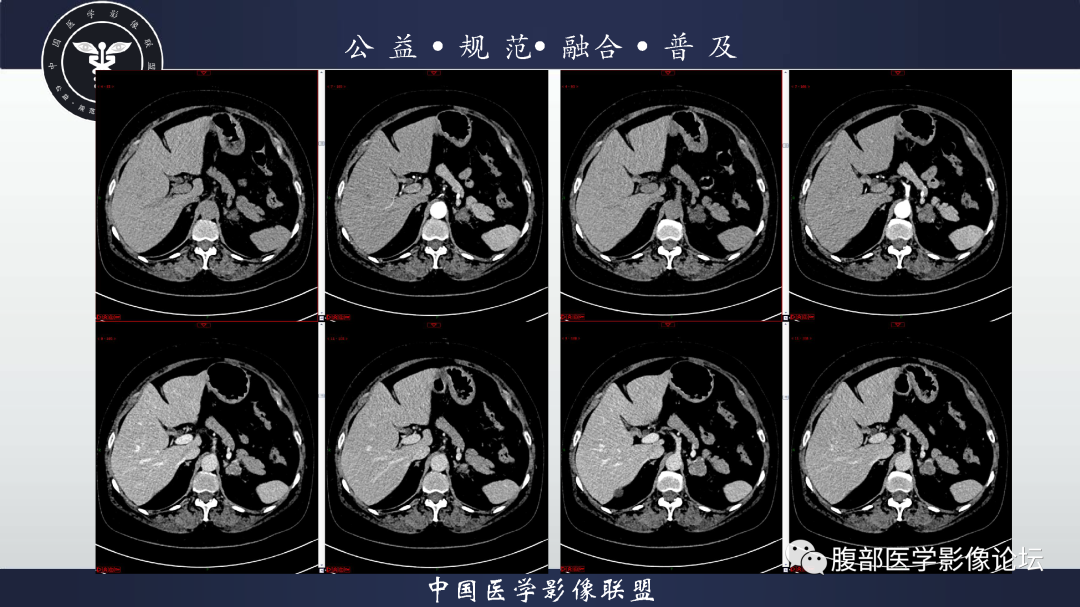

【病例】肾脏透明细胞癌1例CT影像-3